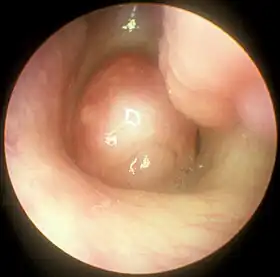

Large nasal polyp (round mass, center), which is commonly treated and removed by FESS | |

Functional endoscopic sinus surgery is most commonly used to treat chronic rhinosinusitis (CRS),[8] only after all non-surgical treatment options such as antibiotics, topical nasal corticosteroids, and nasal lavage with saline solutions[9] have been exhausted. CRS is an inflammatory condition in which the nose and at least one sinus become swollen and interfere with mucus drainage.[9] It can be caused by anatomical factors such as a deviated septum or nasal polyps (growths), as well as infection. Symptoms include difficulty breathing through the nose, swelling and pain around the nose and eyes, postnasal drainage down the throat, and difficulty sleeping.[10] CRS is a common condition in children and young adults.[11]

The purpose of FESS in treatment of CRS is to remove any anatomical obstructions that prevent proper mucosal drainage. A standard FESS includes removal of the uncinate process, and opening of the ethmoid air cells and Haller cells[12] as well as the maxillary ostium, if necessary. If any nasal polyps obstructing ventilation or drainage are present, they are also removed.[8] In the case of paranasal sinus/nasal cavity tumors (benign or cancerous), an otolaryngologist can perform FESS to remove the growths, sometimes with the help of a neurosurgeon, depending on the extent of the tumor. In some cases, a graft of bone or skin is placed by FESS to repair damages by the tumor.[13]